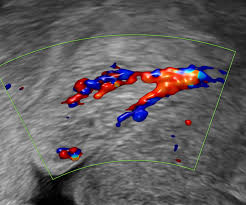

Diagnosis And Management Of Adnexal Masses American Family Physician from www.aafp.org Ovarian cancer includes a heterogeneous group of malignancies that arise from the various cell types that compose the ovary. 3 weeks after this bleeding doctor did an endometrial biopsy and said my lining was very thin. Relative and attributable risks of cardiovascular disease, cancer, and other health outcomes. But the ovaries do also continue to make androgens which can help with libido and some of the androgens are converted into estrogen. I was worried about endometrial. Pmb can be caused by vaginal, cervical, uterine or ovarian. While vaginal bleeding has been known to be a symptom of endometrial cancer, this large study confirms the practice of. The risk for developing ovarian cancer appears to be affected by several factors.

Rare causes of postmenopausal bleeding include: Ovarian cancer met at 15 women with postmenopausal bleeding that of 0.85% of the total number of women with bleeding menopause and 1,23% of all patients with malignant tumors. Webmd explains possible causes of bleeding, which should always be checked out by a doctor. Vaginal bleeding after the menopause is not normally expected and there may be a number of different causes of postmenopausal endometrial cancer: Do i have ovarian cancer? Because vaginal bleeding after menopause can be a symptom of endometrial cancer, this often leads to further testing. In most cases, postmenopausal bleeding is caused by issues such as endometrial atrophy (a thinning of the uterine lining), vaginal atrophy, fibroids, or endometrial polyps. , post menopausal cramping and bleeding for 4 days, have had gi problems most my life. After extensive examination and discussion, ovarian carcinoma was suggested. While vaginal bleeding has been known to be a symptom of endometrial cancer, this large study confirms the practice of. Ovarian cancer is a malignancy arising from the ovary. A number of conditions may lead to postmenopausal bleeding Women who have become amenorrheic for at least six months can be considered menopausal.

Had same problems 20 years ago without bleeding. Most commonly it is found occurring in women who are older than 50. Mr angus mcindoe, a top gynaecologist, explains how it is diagnosed. It is the leading cause of death from gynaecological cancer3. Early ovarian cancer may not cause obvious symptoms. Ovarian cancer met at 15 women with postmenopausal bleeding that of 0.85% of the total number of women with bleeding menopause and 1,23% of all patients with malignant tumors. The risk for developing ovarian cancer appears to be affected by several factors. While vaginal bleeding has been known to be a symptom of endometrial cancer, this large study confirms the practice of. Ovarian cancer includes a heterogeneous group of malignancies that arise from the various cell types that compose the ovary. At age 52 the amount of estrogen an ovary produces is typically small. , post menopausal cramping and bleeding for 4 days, have had gi problems most my life. Pmb can be caused by vaginal, cervical, uterine or ovarian. Malignant ovarian lesions include primary lesions arising from normal structures within the ovary and secondary lesions from cancers arising elsewhere in the.